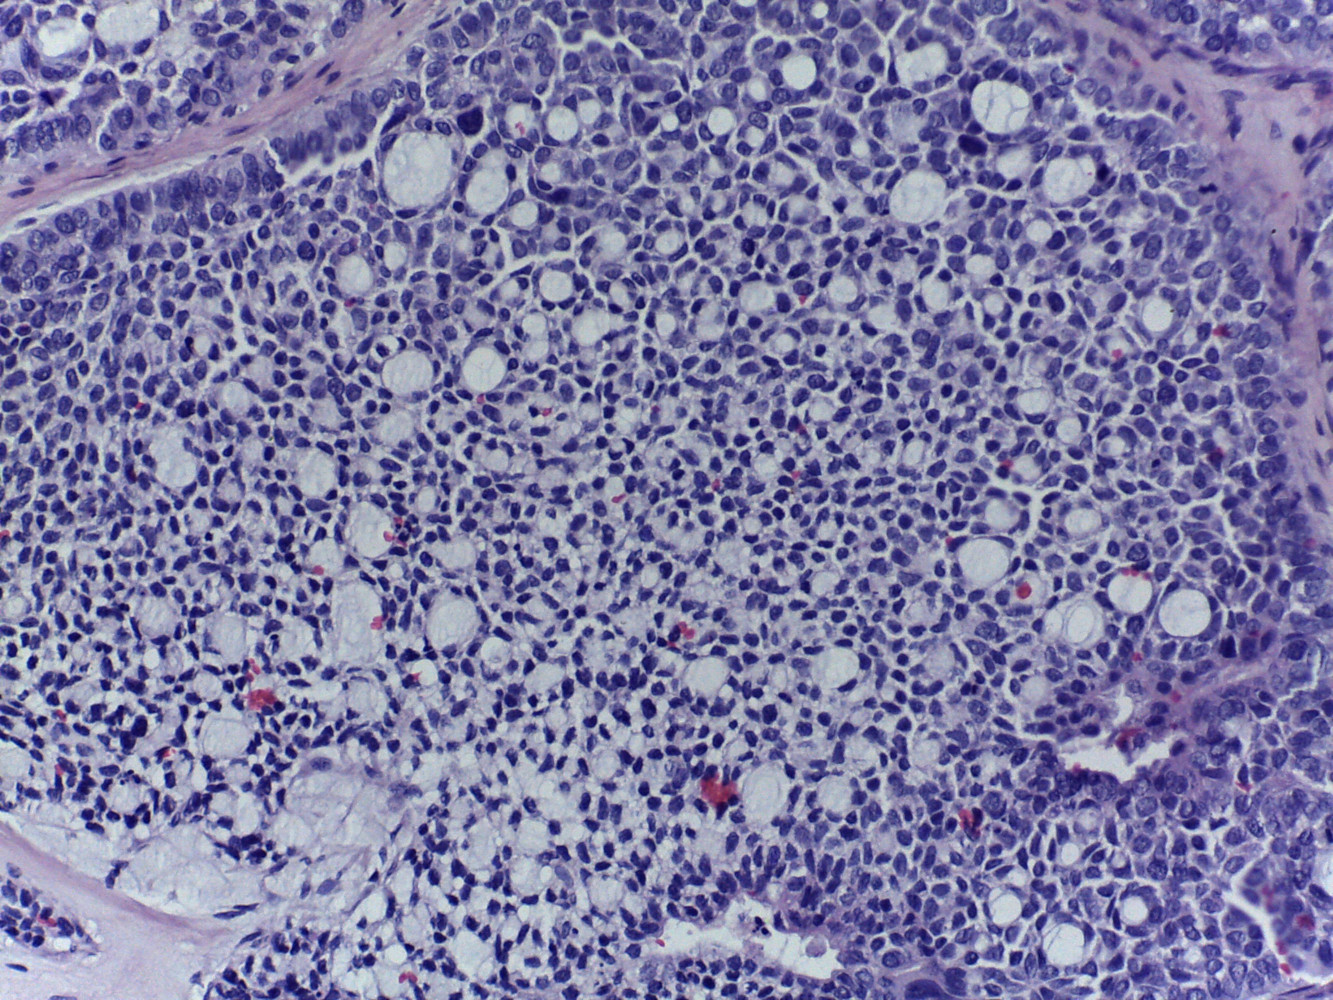

Diagnóstico: Carcinoma multifenotipico sinonasal asociado a VPH

Comentario: Anteriormente conocido como carcinoma con características semejantes al carcinoma adenoideo quístico asociado a VPH, este carcinoma se ha descrito hasta ahora solamente en tracto sinonasal, tiene características histológicas semejantes al carcinoma adenoideo quístico con componente cribiforme y tubular y un componente de carcinoma epidermoide in situ en el epitelio superficial . Todos los casos descritos están asociados a infección por VPH .